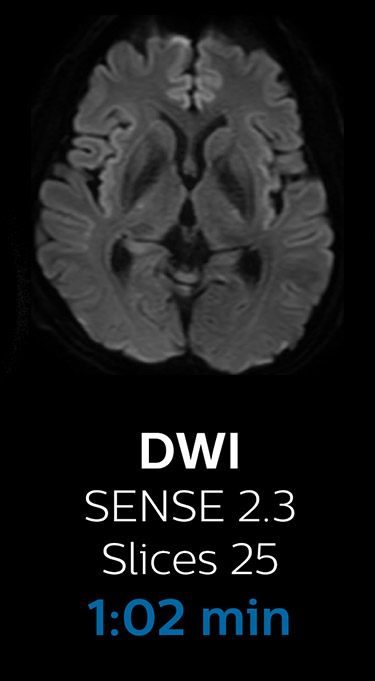

Fast MRI of brain

With Compressed SENSE, the scan time for the routine brain examination at KNC was reduced from 15:48 to 10:19 minutes, which corresponds to 35% reduction.

Brain without Compressed SENSE

Brain with Compressed SENSE

Ingenia 3.0T CX

Scan time 15:48 min.

Scan time 10:19 min.